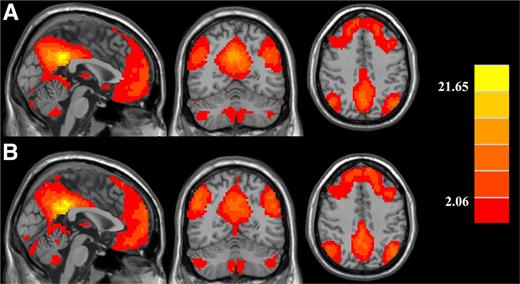

The PCC showed strong functional connectivity to a number of other brain regions in both the healthy controls and the diabetic patients. These regions included the anterior cingulate cortex, PCC, inferior parietal lobe, MFG, and temporal lobes, which were in line with the DMN regions (10). Besides, several other regions, such as the cerebellum posterior lobe, the superior frontal gyrus, the postcentral gyrus, and the parahippocampa gyrus also exhibited similar changes (Fig. 1).

Significant brain functional connectivity to the PCC using one-sample t test in (A) healthy controls and (B) type 2 diabetic patients. Thresholds were set at a corrected P < 0.05, determined by Monte Carlo simulation. Note that the left side corresponds to the right hemisphere.